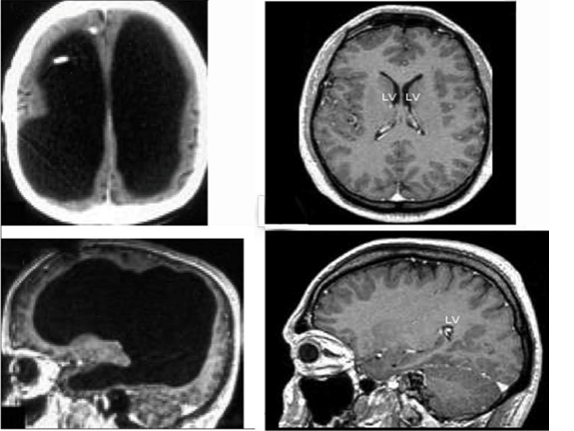

За сравнение, от лявата страна е мозъкът на човека, а от дясната страна е мозъкът на обикновен човек.